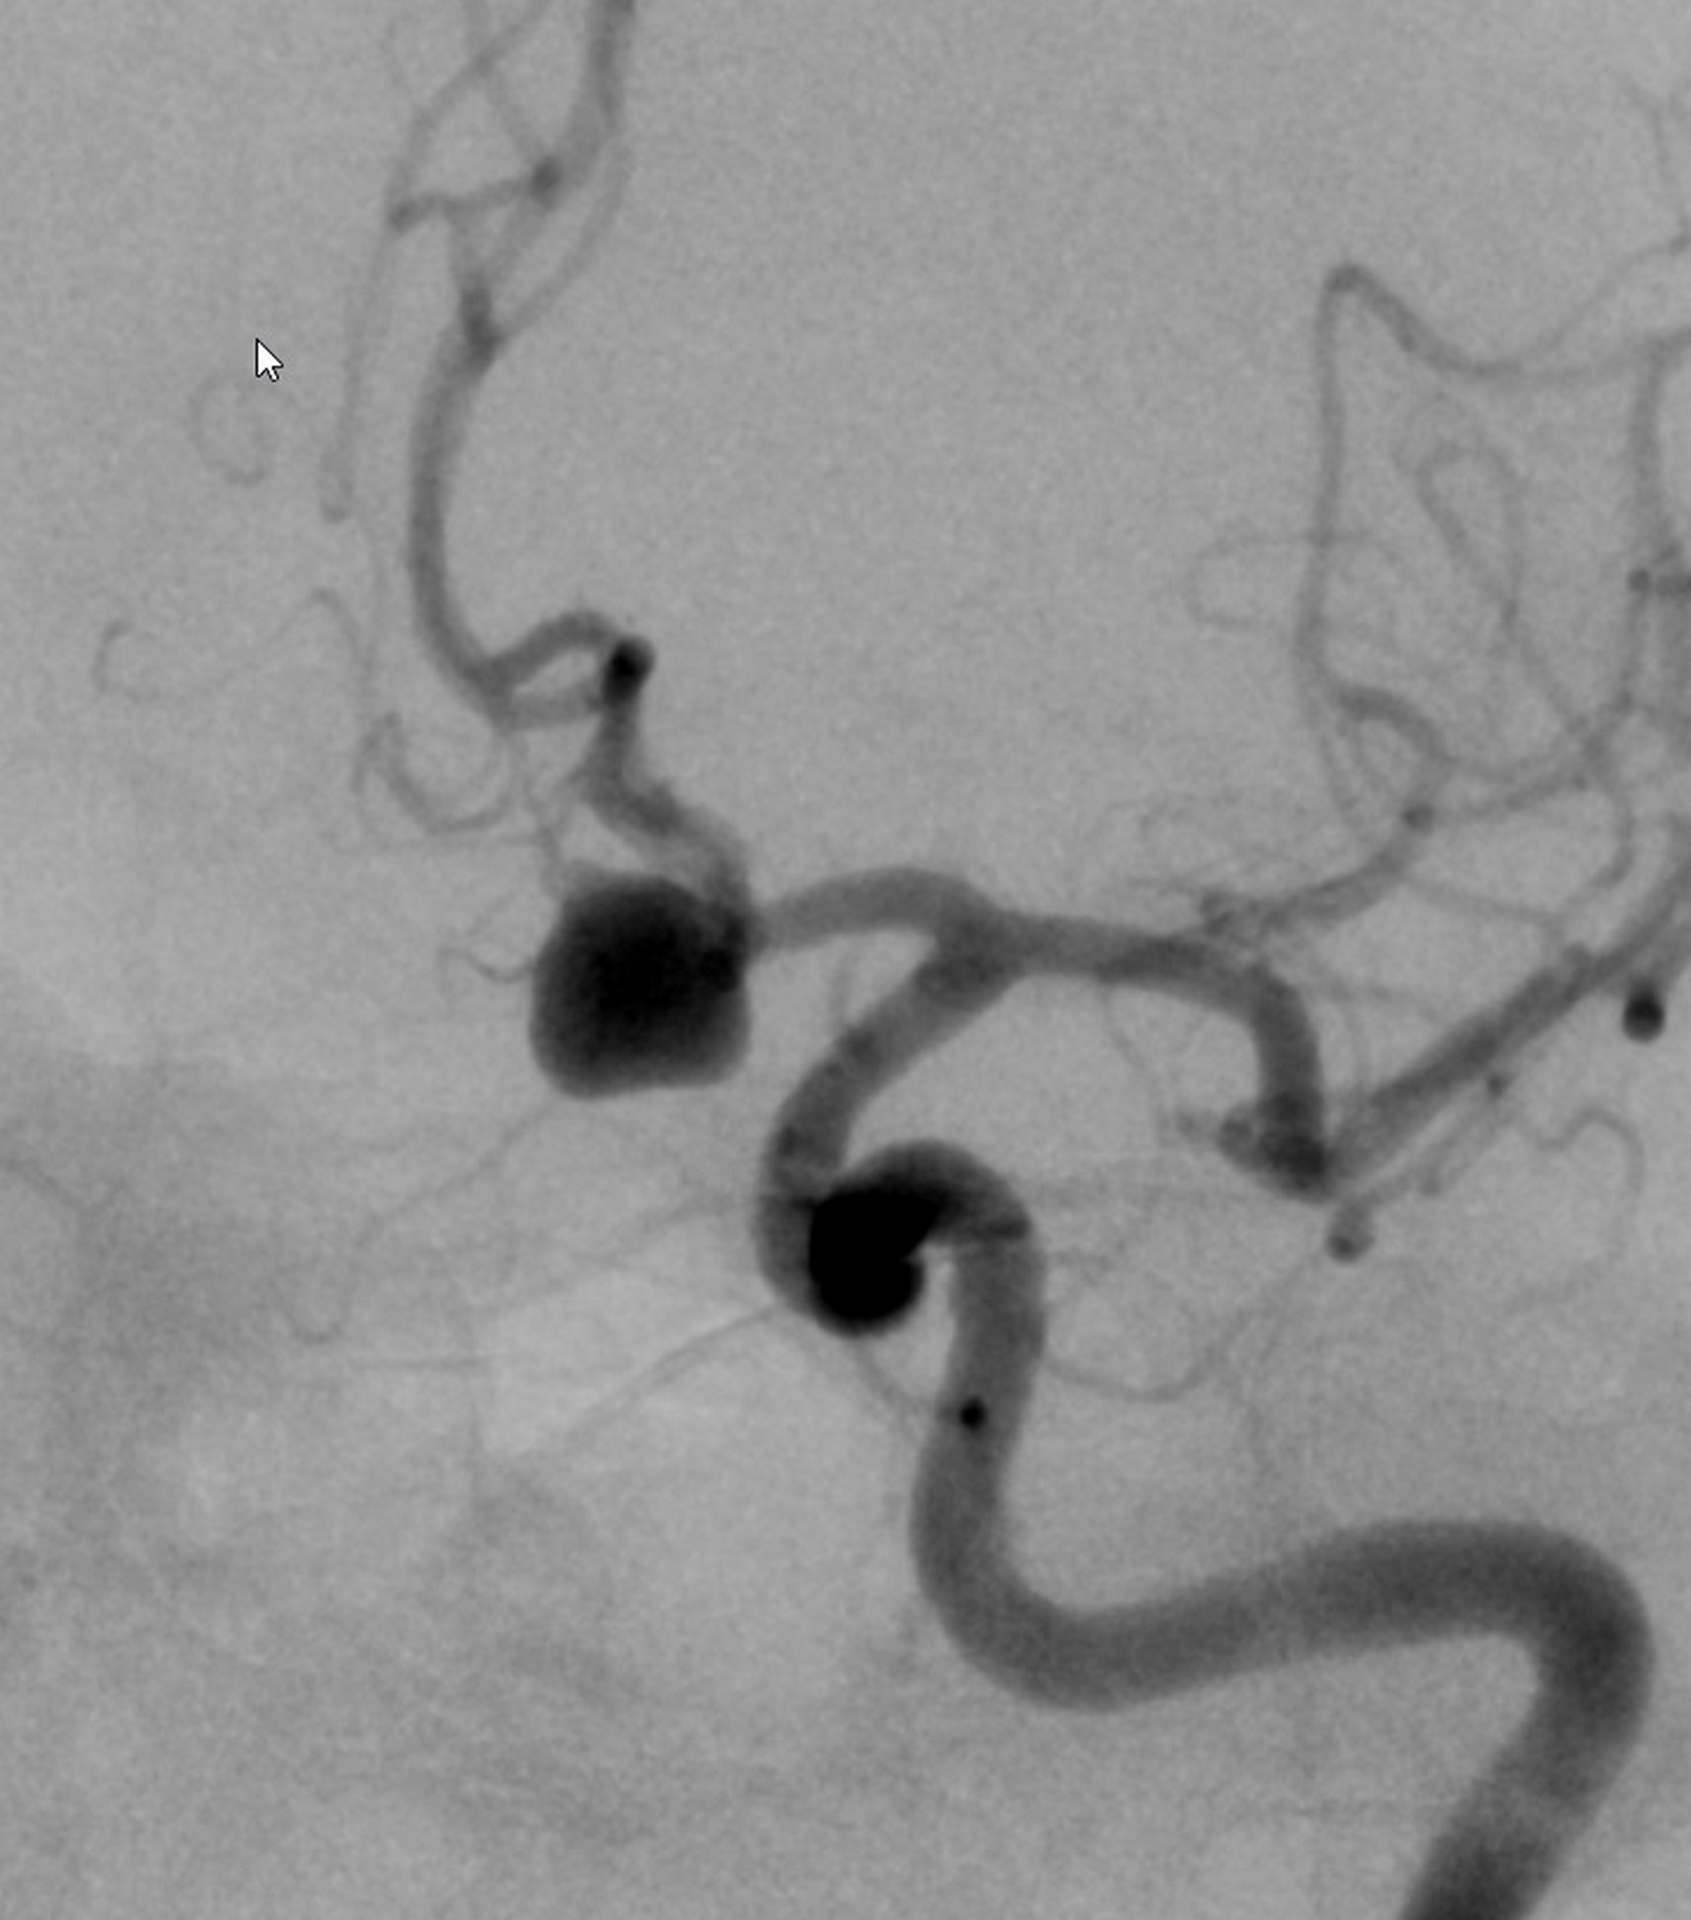

Naturalnie nie. W pierwszej fazie stosowania technik przeznaczyniowych notowano wysoki odsetek nawrotów tętniaka po embolizacji (tzw. rekanalizacja tętniaka) i związanej z tym konieczności powtórnego leczenia. Głównym powodem nawrotów było niewystarczające wypełnienie worka tętniaka spiralami embolizacyjnymi (zobacz rysunek poniżej). Fakt ten stał się jednym z głównych motorów napędowych rozwoju technologicznego sprzętu wykorzystywanego w leczeniu endowaskularnym, jak również nieustających poszukiwań technik embolizacji trwalszych i skuteczniejszych niż metoda klasyczna.

Rysunek 4. Skala Raymonda. Stopień 1 – tętniak całkowicie wypełniony; stopień 2 – resztkowa szyja tętniaka; stopień 3 – tętniak resztkowy . Kolorem czarnym oznaczono przepływającą krew.